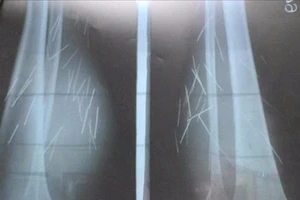

70 cây đinh tự trồi ra khỏi chân 1 phụ nữ